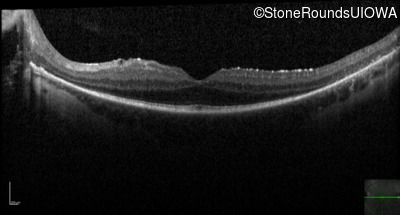

Optical Coherence Tomography - Left - 20/32 -1

Exemplar / OCT Stack

OCT Stack